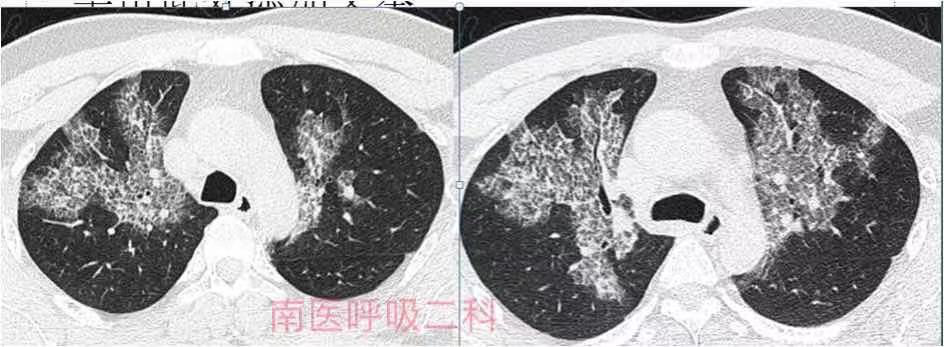

经过检查发现,潘先生胸部CT呈磨玻璃影,小叶间隔增厚伴有实变,乍一看就像一张“地图”。医生初步诊断为肺泡蛋白沉积症,经过针对性检查后果然确诊。